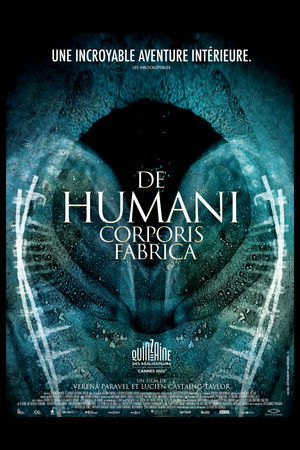

De humani corporis fabrica

(2023)Overview

An extraordinary adventure through the interior of the human body; or the discovery of an alien landscape of unprecedented beauty.